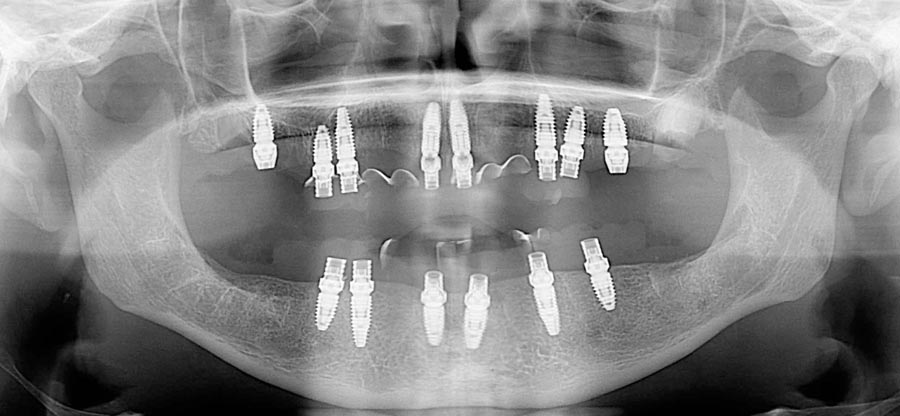

Her panoramic radiograph shows multiple missing and broken teeth along with tooth decay and areas of infection spreading into the bone.